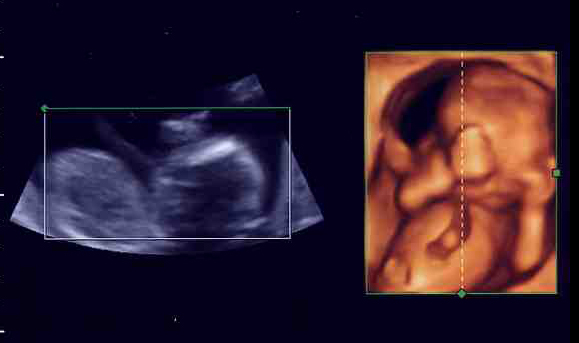

左は、9週目の「私」。右は29週になった「私」。

下の写真を見比べてみて。今までのエコー写真は白黒で、シルエットがぼんやり写るぐらい(左写真)。右の4D写真だと、「私」の手の指も、顔の輪郭も、臍帯まではっきり見えるでしょ?

先生の説明だと、モノが立体に見える「3D画像」を時間を追ってみられるから「4D」と呼ぶんだそうです。1秒間に6回画像が更新されて、映像を見ているみたいにリアルなんだって。手で顔をこすったり、あくびをしたり、足を握ったリ、キックしたり。しかめ面や微笑む顔まで、よーくわかるらしいの。ママの臍帯を握って安心している様子も見られちゃう(下写真)。ママは「ああ、お腹の中で生きてるんだなあ」って実感がわいて、とても感動するみたい。